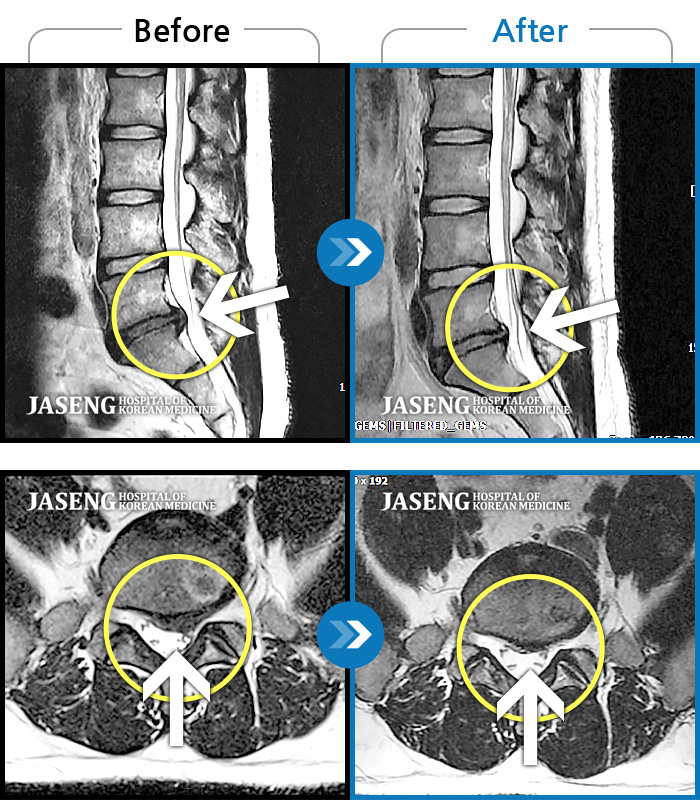

목디스크

도움받은 사례

목동 · 고웅 원장

목통증, 왼쪽 팔저림, 두통, 잇몸통증까지 심해 일상생활 불가

촬영시기

2022.08.20 ~ 2024.02.24

2024.12.24